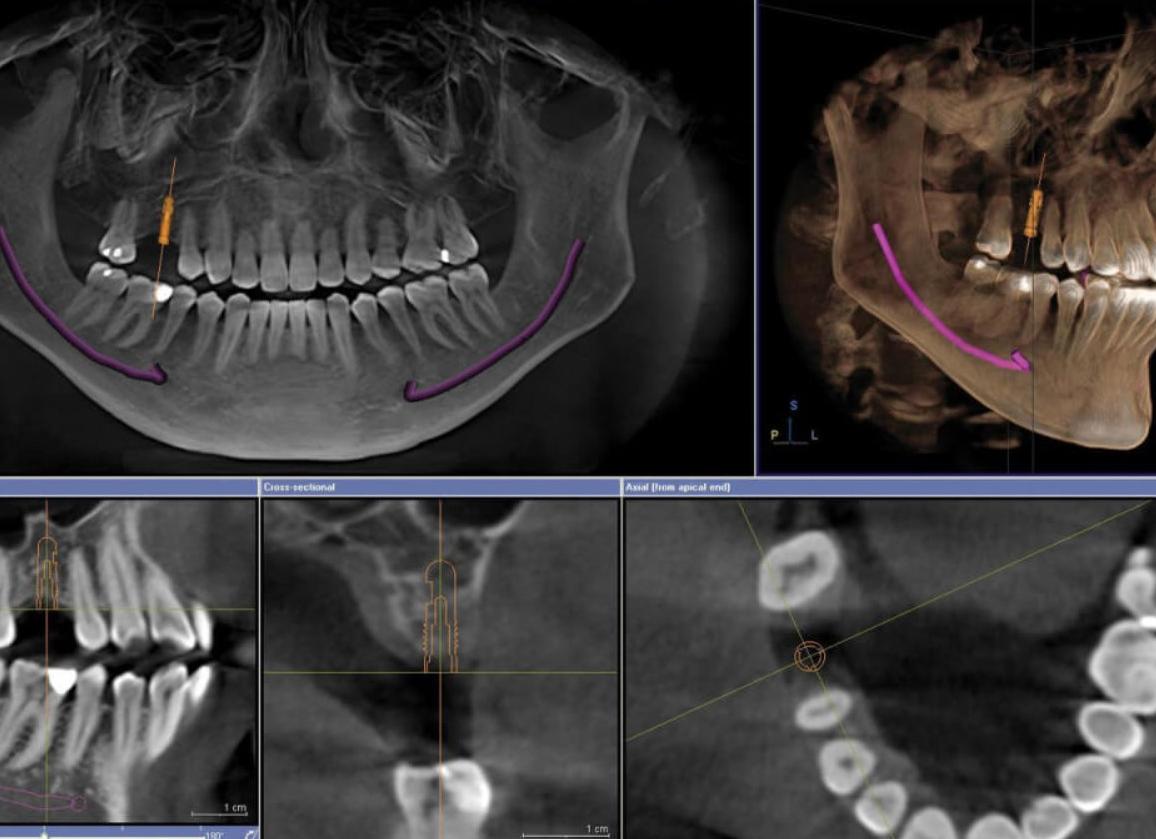

3D компьютерная томография зубов, которую можно проводить при помощи стоматологических конусно-лучевых томографов, позволяет получать объемные модели зубов, челюстей и других органов и анатомических образований. Эти объемные модели можно рассмотреть со всех сторон, увеличить, чтобы заметить мелкие детали. Все это значительно облегчает задачу врачу, которому больше не приходится действовать вслепую при проведении хирургической операции или протезирования.

На 3D-снимке отображено неограниченное количество срезов зубочелюстной системы, сделанных под разными углами и в разных плоскостях. Такая полнота обследования позволяет изучить все особенности и обнаружить малейшие изменения анатомии.

Поскольку информация, собранная на этапе сканирования зубов томографом, прошла обработку и преобразование с помощью специальной компьютерной программы, 3D-снимок показывает точнейшие изображения твердых и мягких тканей челюсти. В результате у врача появляется уникальная возможность: оценить состояние каждого зуба. Причем, увидеть не только, что происходит внутри, но и вокруг него: 3D-снимок создается по принципу «один к одному», поэтому искажение изображения и ошибки интерпретации исключены.

Цифровые снимки высокого разрешения и качества позволяют осуществить сканирование интересующей врачей области в различной плоскости:

• фронтальная – обозначена синим цветом (см. фото);

• сагиттальная или вертикальная, делит объект на левую и правую половины (красный);

• аксиальная – поперечная, делит на верхнюю и нижнюю части (зелёный).

Такие томографические исследования предоставляют рентгенологам полную информацию о состоянии пациента, кроме этого, появляется возможность построения 3D моделей в различных сечениях, выполнения более точных измерений.